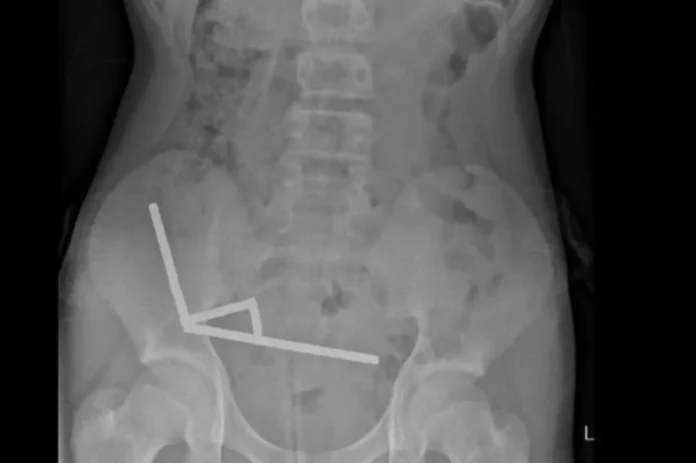

Exames indicaram que os ímãs estavam agrupados em quatro cadeias dentro do abdômen, atraindo partes diferentes do intestino. Essa forte força magnética causou necrose por pressão no tecido, o que exigiu ação cirúrgica imediata.

Durante a operação, os cirurgiões removeram os ímãs, mas foi necessário retirar parte do intestino delgado e grosso. O adolescente permaneceu hospitalizado por oito dias antes de receber alta.